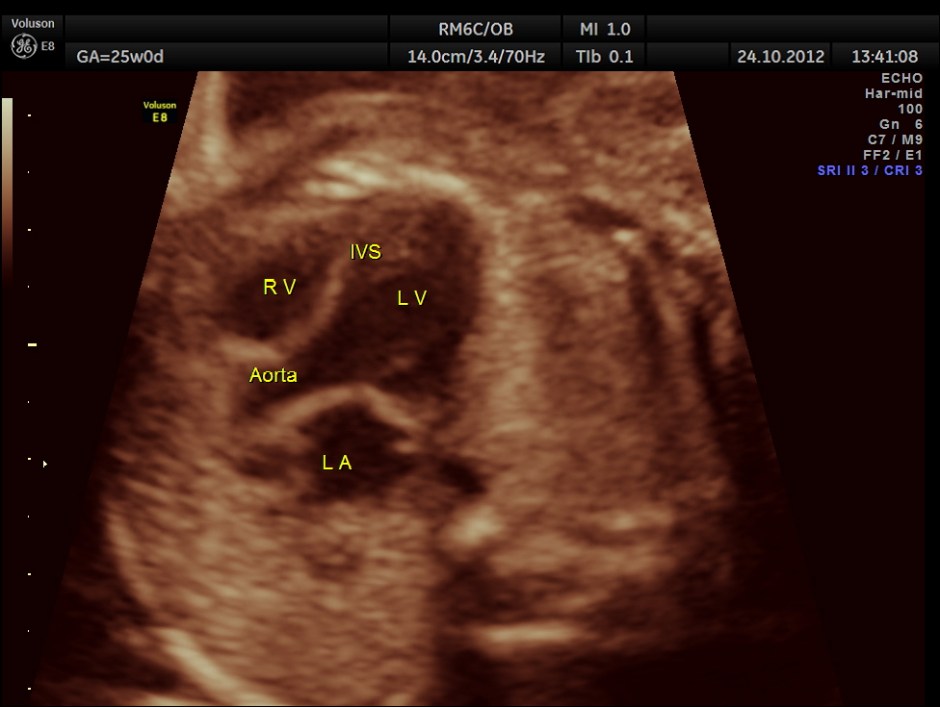

The scan was done around 25 weeks of gestation :

colour flow clearly demonstrating the atrio ventricular septal defect